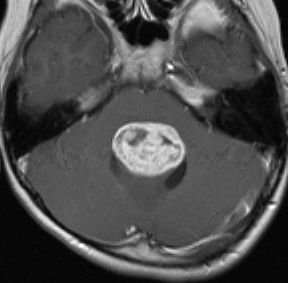

思春期の女の子にできた小脳腫瘍です。とても大きく見えますがほとんどが水たまり(のう胞といいます)。第4脳室が腫瘍で圧迫されて閉塞性水頭症になりました。のう胞の中に出血がありますが毛様細胞性星細胞腫では腫瘍内出血をしばしば見ます。右の写真で脳室が大きくなっています。こんなに大きいのに小脳症状は全くなくて,頭痛と嘔吐が症状でした。

赤で塗ったところだけが毛様細胞性星細胞腫です。これを取れば治ります。簡単な手術ですし後遺症も残りません。

手術後のMRIです。水頭症も改善してますから症状も消失しましたし,すぐに退院です o(^o^)o